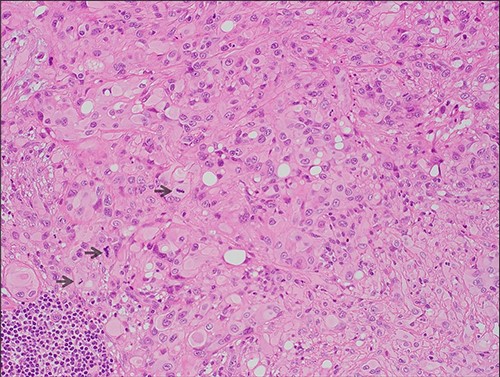

The excised specimen revealed a 13-mm tumor which invaded down to elastic cartilage with ulceration and focal necrosis. The tumor was composed of sheets of epithelioid cells with eosinophilic hyaline cytoplasm and intracytoplasmic vacuoles (Fig. 2).

Microscopic features (x20, H&E) of the lesion which comprises of sheets of epithelioid cells with eosinophilic hyaline cytoplasm; intracytoplasmic lumina and focal pleomorphism are evident; mitotic figures are highlighted by arrows.

The mitotic index was up to 6/10 high-powered fields (HPF). No lymphovascular invasion was observed. The peripheral margin was 1.9 mm and the deep margin was 2 mm. Immunohistochemistry showed positivity for CD31 and the tumor cells were strongly positive for ERG. The pathologic features supported a diagnosis of malignant EH.

The histological and immunohistochemical findings demonstrated in this case are typical of EH. The microscopic features of epithelioid cells with eosinophic hyaline cytoplasm and intracytoplasmic vacuoles are common features of EH [5]. Both ERG and CD31 are highly sensitive for EH, and one case series [5] documented 100% of cases staining positive for these markers.